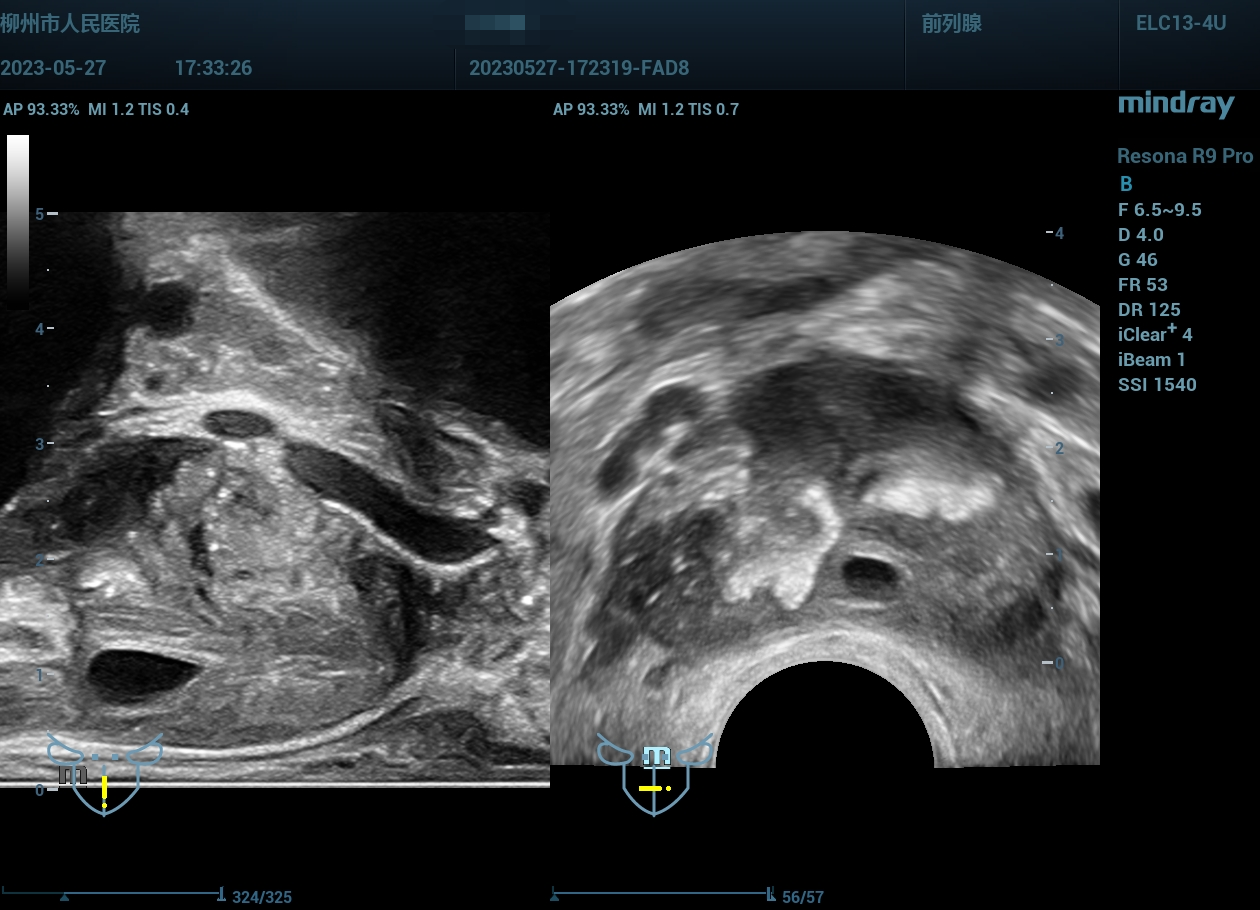

病史为年轻的男性,主要症状为尿痛、血精。

精囊腺的超声图像表现:肿胀、回声紊乱。